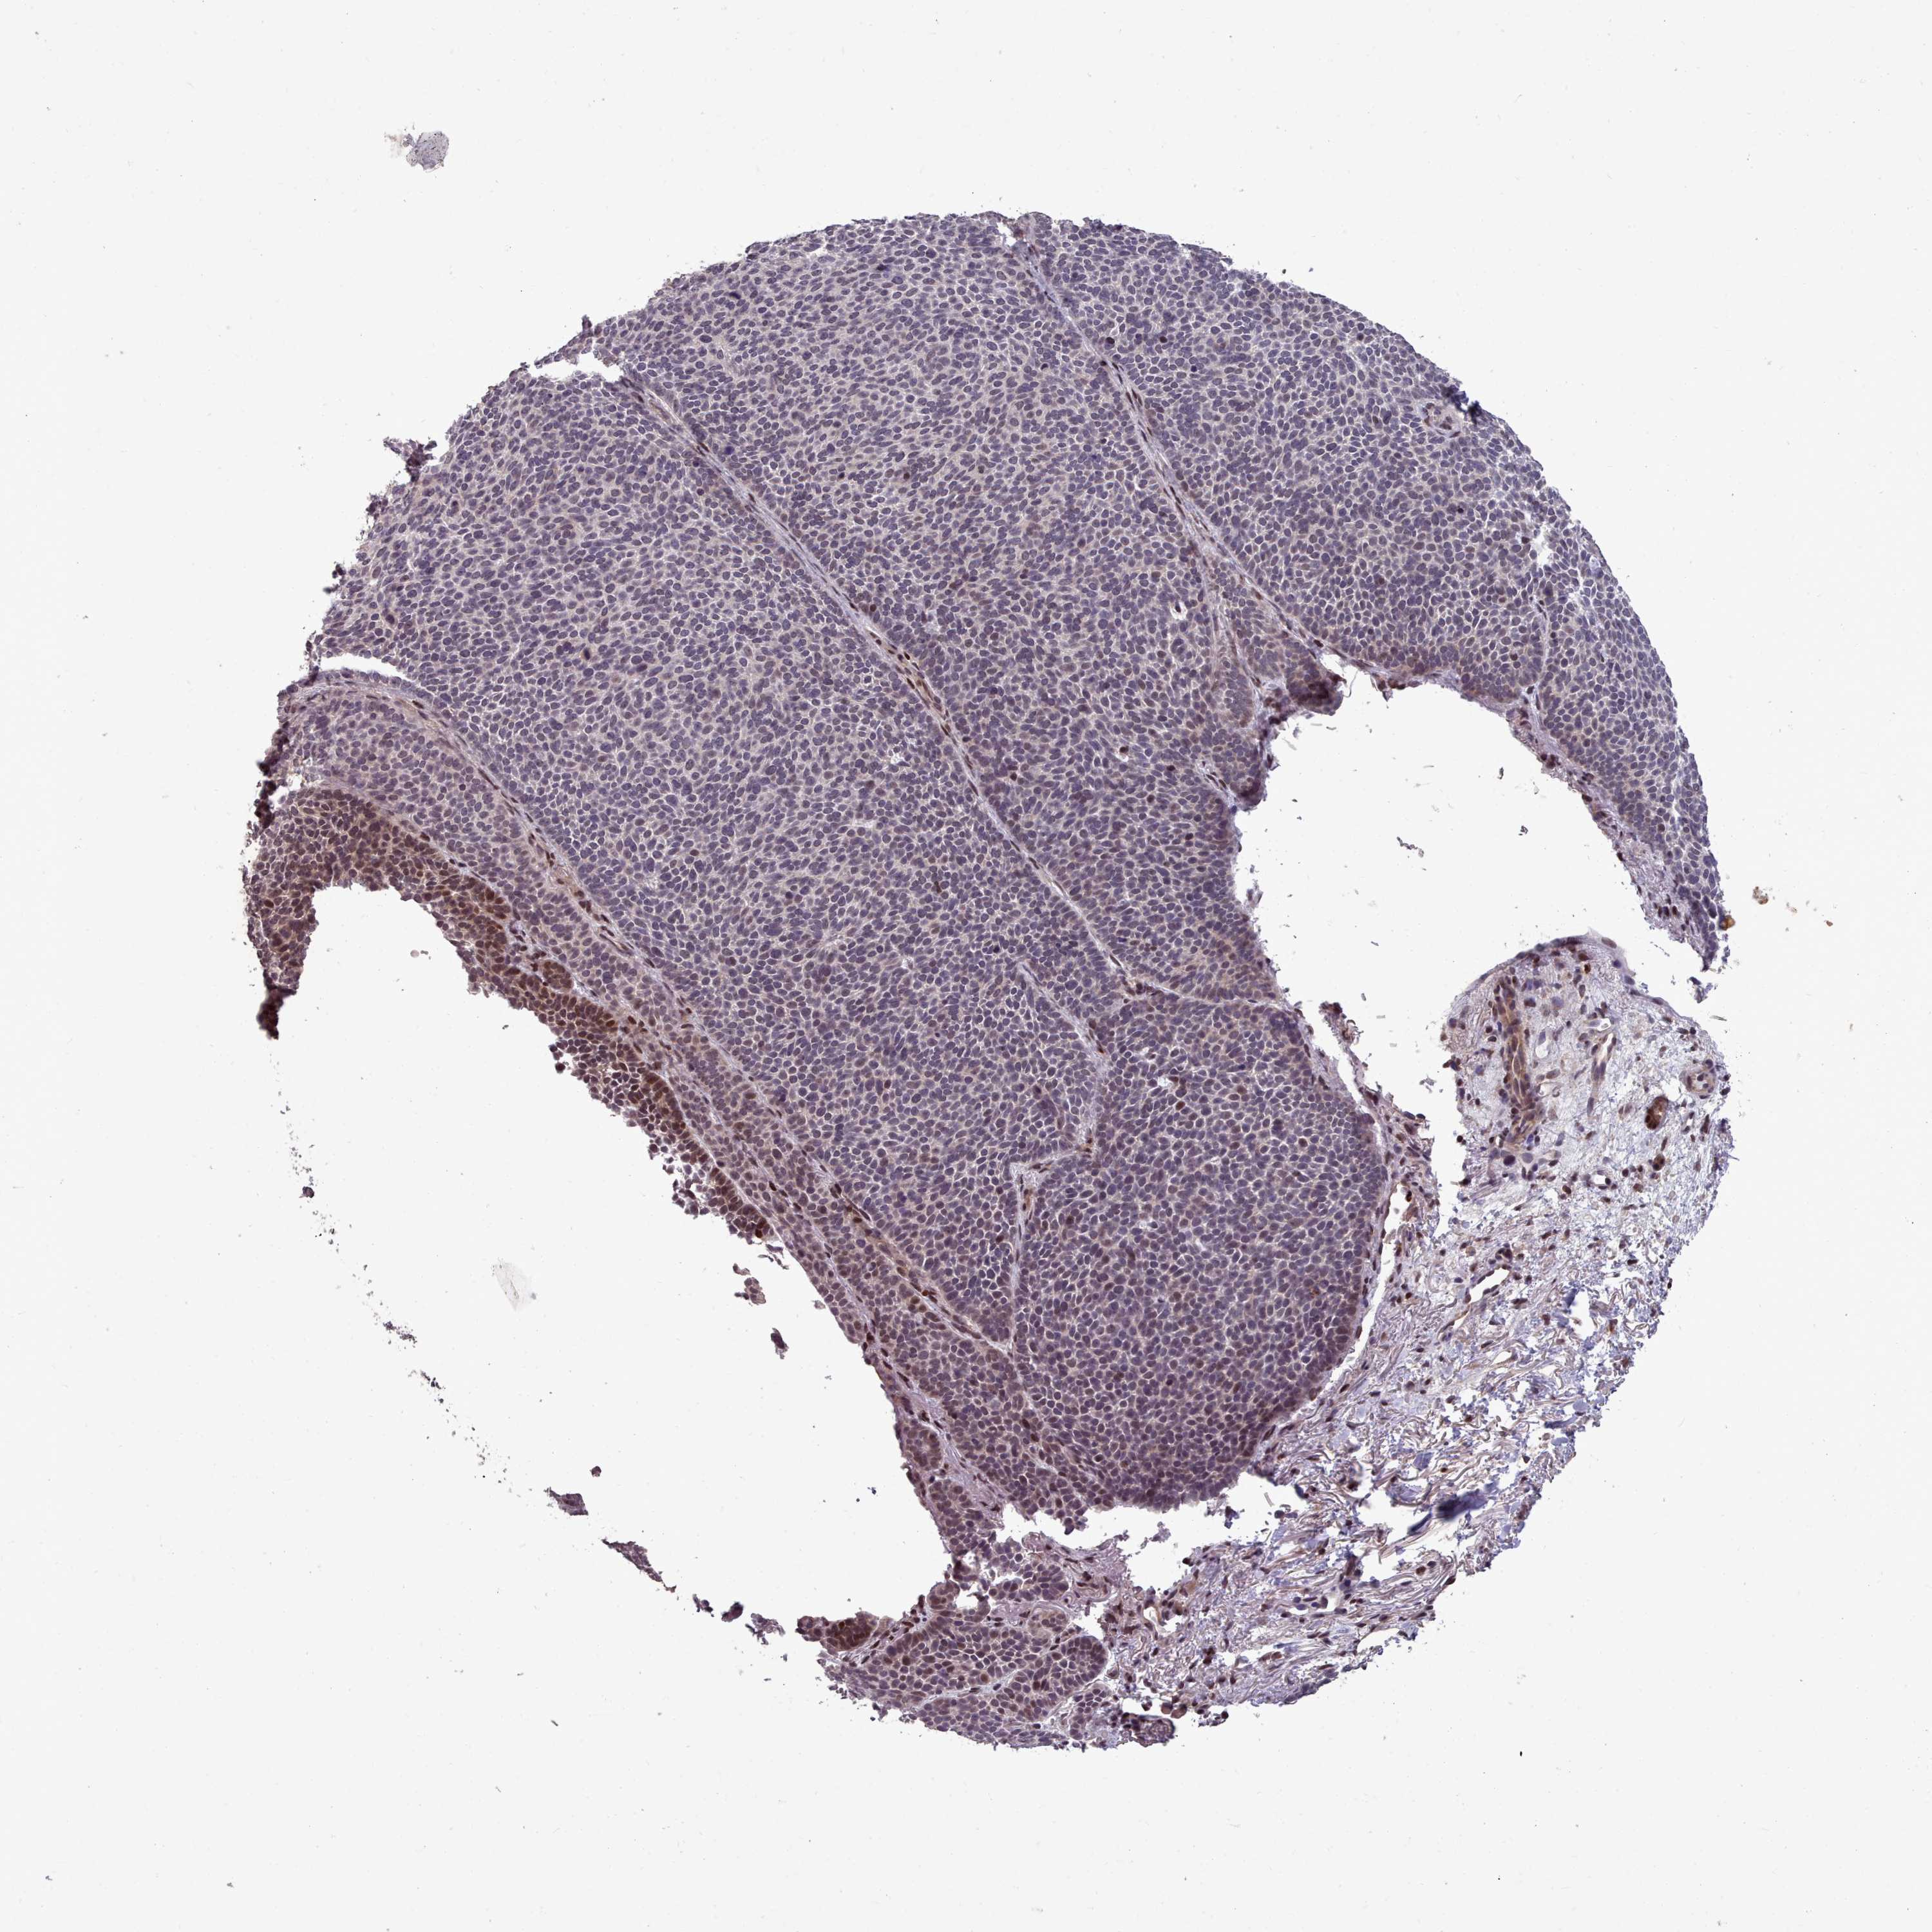

Basal cell and squamous cell cancer

SKIN CANCER - Protein expressioni

A mouse-over function shows sample information and annotation data. Click on an image to view it in a full screen mode. Samples can be filtered based on level of antibody staining by selecting one or several of the following categories: high, medium, low and not detected. The assay and annotation is described here.

Antibody stainingi

Antibody staining in the annotated cell types in the current human tissue is reported as not detected, low, medium, or high, based on conventional immunohistochemistry profiling in selected tissues. This score is based on the combination of the staining intensity and fraction of stained cells.

Each image is clickable and will lead to virtual microscopy that enables deeper exploration of all samples and also displays staining intensity scores, fraction scores and subcellular localization as well as patient and tissue information for each sample.

Antibody HPA051294

Staining

High

Medium

Low

Not detected

Intensity

Strong

Moderate

Weak

Negative

Quantity

>75%

75%-25%

<25%

None

Location

Nuclear

Cytoplasmic/membranous

Cytoplasmic/membranous,nuclear

Basal cell carcinoma